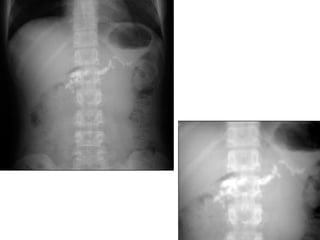

THUÛNG TAÏNG ROÃNG

* Vò trí

o Thöôøng ôû phaàn cao oáng tieâu hoaù (vieâm loeùt, nhieãm truøng,

thuûng do ngoaïi vaät nuoát vaøo…)

o Caùc oáng tieâu hoaù tröôùc coät soáng (chaán thöông)

* Daáu hieäu kinh ñieån: lieàm hôi döôùi hoaønh: xuaát hieän 6-8

giôø sau thuûng vôùi löôïng hôi khoaûng 20-50ml

* Caùc tö theá khaùc: BN nghieâng (T) laáy heát bôø ngoaøi gan vaø

hoá chaäu (P), naèm ngöõa tia phoùng ngang…